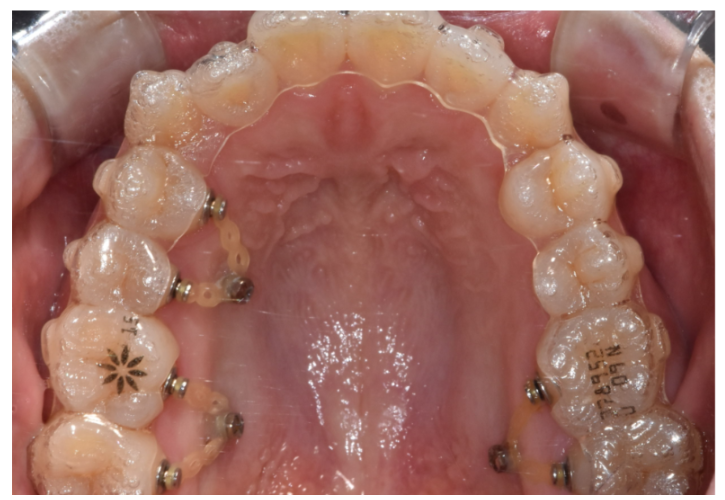

230617 고무줄, 미니스크류와 같은 보조장치

필요한 경우 추가 검사나

보조장치를 달아

대응을 하고 있습니다.